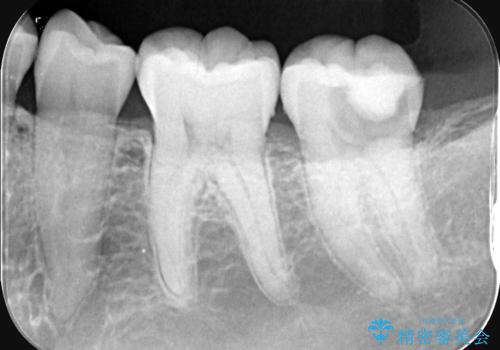

- 昨日からのズキズキとした激しい痛みを主訴にご来院されました。レントゲンおよび歯髄診察の結果、不可逆性の歯髄炎(歯の神経の重度の炎症)と診断。歯を残すことを第一に、まず痛みの原因である神経を取り除く根管治療を提案しました。また、虫歯が歯肉の下まで深く進行していたため、根管治療後に歯周外科処置を行い、最終的に精密なセラミッククラウンで修復する、総合的な治療計画を立案しました。

治療はまず、根管治療から始め、感染した神経を徹底的に除去することで、痛みをすぐに解消しました。再発を防ぐため、ラバーダムや顕微鏡を使って、根管内を丁寧に、そして精密に処置しました。次に、深い部分の虫歯を確実に治療するため、歯周外科処置を行い、治療しやすい環境を整えました。最後に、機能と見た目に優れたセラミッククラウンを作製・装着。根管治療から外科処置、審美修復までを一貫して行うことで、再発リスクの低い、長期的に安定して使える奥歯を取り戻していただけました。